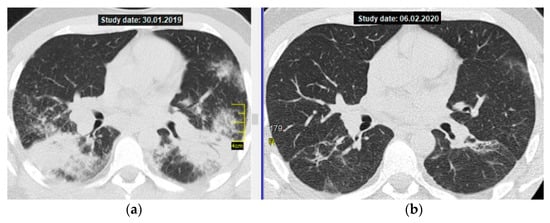

Figure 2 shows CT axial sections, on the left—on the day of diagnosis, on the right—after the end of methotrexate therapy.

Figure 2. Pulmonary sarcoidosis, stage II, atypical form—multiple massive consolidations in both lungs; a thoracic CT scan (axial section at the level of division of the main bronchi): (a) on the left—before treatment, (b) on the right—after 12 months of MTX therapy, 15 mg/week (complete resolution with residual changes in the form of limited interstitial fibrosis).